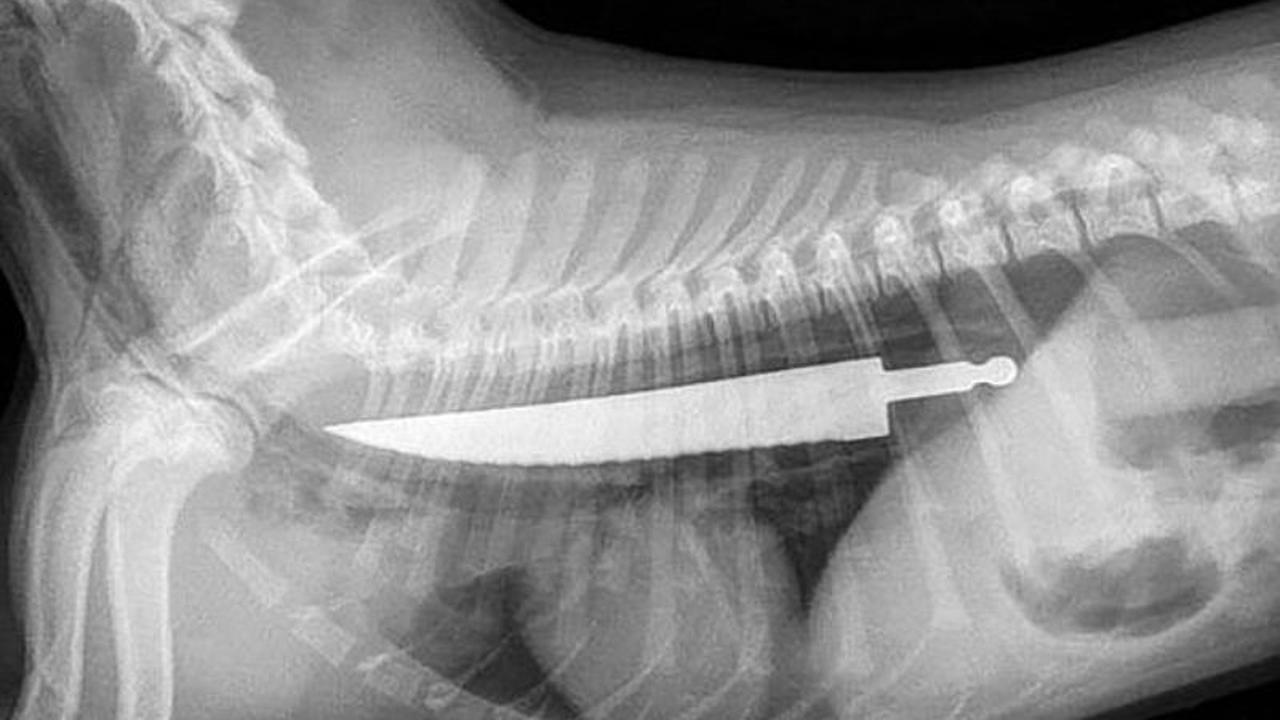

Liputan6.com, Jakarta - Mungkin ini terdengar tak masuk akal, tapi benar terjadi. Hasil foto x-ray menunjukkan pisau sepanjang 20 cm ditelan oleh anjing, yang secara ajaib selamat. Lalu, bagaimana ceritanya?

Dokter hewan yang memeriksa Lexi kaget saat melihat hasil foto x-ray. Di foto tersebut, tampak pisau sepanjang 20 cm dalam perut Lexi. Setelah menghabiskan waktu 45 menit, barulah dokter hewan di Rumah Sakit Hewan di Sydney bisa mengeluarkan pisau tanpa melukai isi perut anjing itu.

"Aku belum pernah melihat yang seperti ini. Kalau tidak segera diangkat, Lexi tak akan bertahan lebih lama," tutur Dr Jody Braddock, seperti melansir dari Mirror, Rabu (24/08/2016).

"Kami mesti menggunakan kamera sedemikian rupa agar bisa menarik pisau dengan tang lewat mulut, tanpa melukai tubuh Lexi."